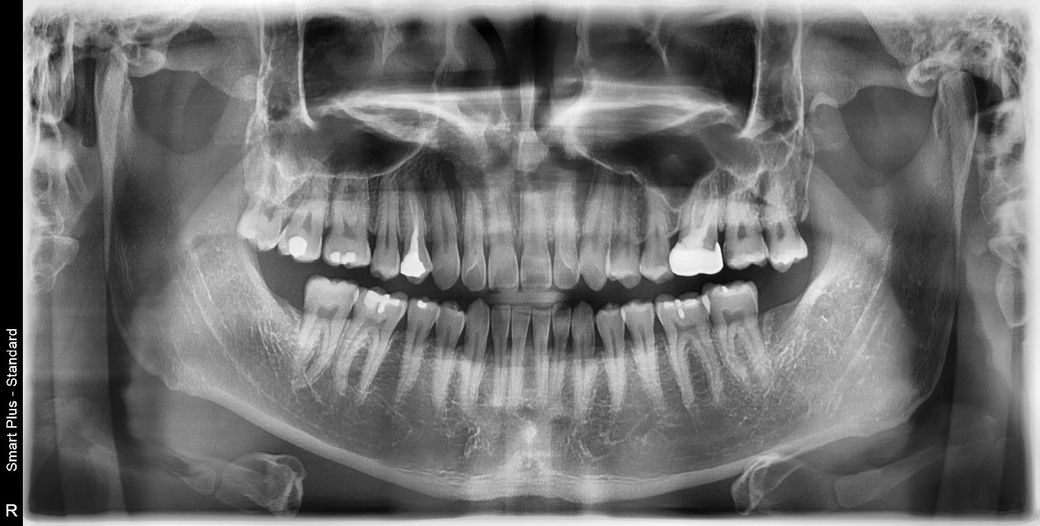

금니 앞쪽 작은어금니는 사진으로 보기에는 신경치료 할 가능성이 더 높아보입니다. 충치를 제거하다보면 신경이 드러날 가능성이 높긴 한데 조그만 방사선 사진을 찍어보면 조금 더 정확히 알 수 있겠습니다. 신경치료는 안할 수 있다면 안하는 것이 좋으니 인레이로 가능하다고 하시는 병원에서 시작하시는 것도 좋아보입니다.

확실히 충치는 있긴하지만 신경과의 거리가 아주 가깝진 않습니다. 물론 충치를 제거하다보면 비의도적으로 신경이 노출될 수도 있습니다. 그런 경우에는 신경치료가 불가피하나 일단은 인레이를 목표로 치료 들어가볼 것 같습니다.

금 크라운의 경우 사용을 하다보면 마모가 되서 구멍이 뚤리기도 합니다. 저정도는 조금더 사용하셔도 될것같습니다. 충치 하나가 상당히 깊어 보여서 신경치료 가능성이 있어 보입니다.